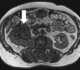

Unilateral absence or blurring of renal outline

May Be Caused by